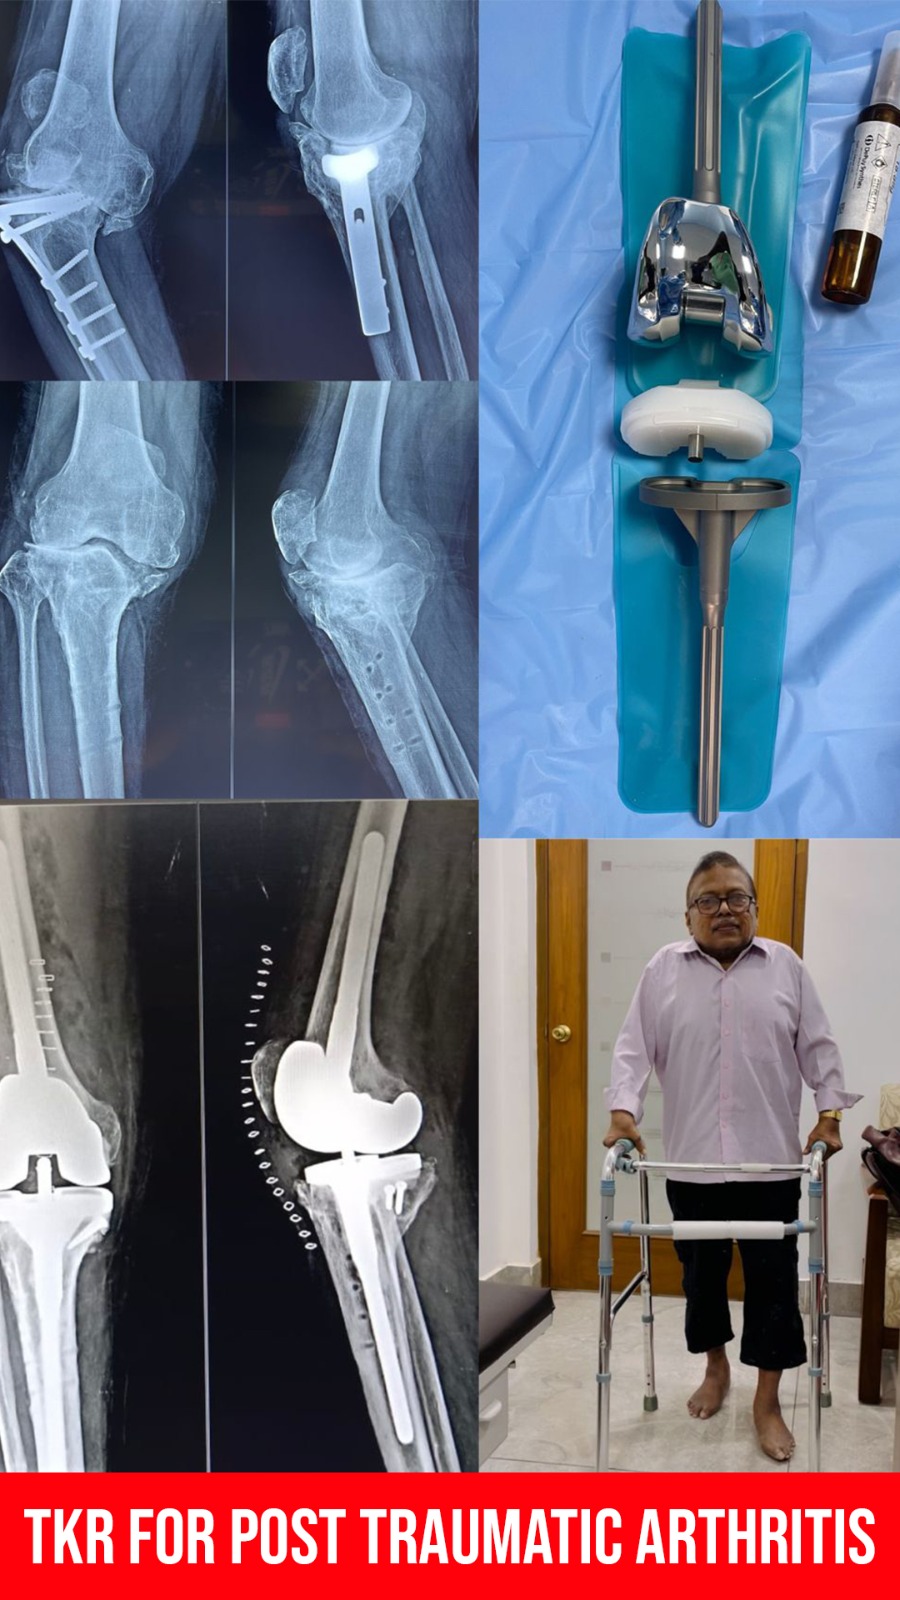

Dr. Giridhar Boyapati is a leading Orthopedic & Joint Replacement Surgeon in Guntur. He has a comprehensive understanding & utilizes various approaches in performing Replacement surgeries depending on the needs of his patients. He has been extensively trained in UK, USA, and India with special expertise in Computer Assisted Joint replacement.